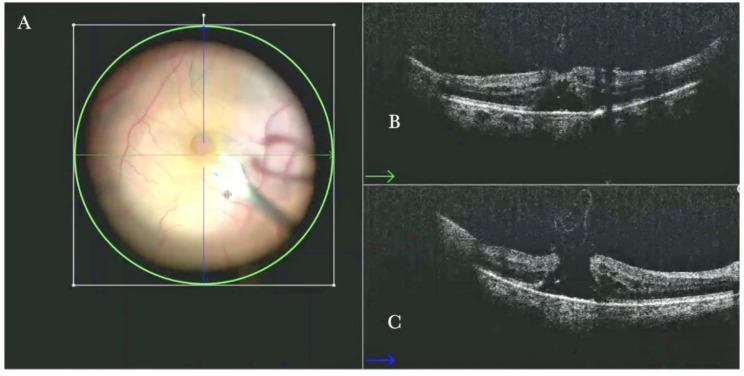

术中光学相干断层扫描在实际玻璃体视网膜手术中的作用

The Role of the Intraoperative Optical Coherence Tomography for Vitreoretinal Surgery in a Real-Life Setting.

To descriptively report the advantages and the feasibility of microscope-integrated intraoperative optical coherence tomography (i-OCT) in managing different vitreoretinal diseases in a real-life setting.

METHODS

We conducted an observational retrospective study involving 265 eyes that underwent elective retinal surgery and intraoperative OCT between 1 September 2018 and 1 October 2022 at Eyecare Clinic (Brescia, Italy).

RESULTS

52 epiretinal membranes, 30 retinal detachments, 60 high myopic eyes, 30 choroidal transplants, 40 macular holes, and 32 vitreo-proliferative retinopathies underwent vitreoretinal surgery and intraoperative OCT scans. The i-OCT was a useful diagnostic exam for all cases and significantly influenced our surgical management.

CONCLUSIONS

i-OCT is a helpful surgical tool in ophthalmic surgery as it provides real-time feedback of tissue anatomy to surgeons, thereby guiding decision-making. Moreover, it provides additional information on the microarchitectural changes after instrument-tissue interactions, further guiding procedures when necessary and possibly reducing unessential surgical maneuvers.